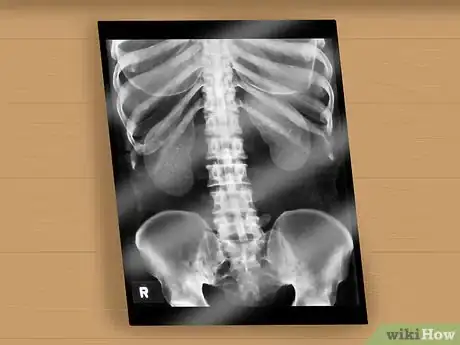

8Get a spinal column x-ray, MRI, or CT scan. Usually this is for spina bifida occulta (SBO), the mildest form of spina bifida, but it can confirm other types as well. The primary method of discovering forms of SBO that may cause problems is an x-ray that can detect a small gap or abnormality of the spine, or less often a spinal cord that is tethered, thickened, contains a fatty lump, is split in two, or connected to skin. This can also be detected using magnetic resonance imaging (MRI), or computed tomography (CT) scan. Most people with SBO don't have any problems. However, there may be some other associated symptoms with SBO, such as:

- Pain, numbness, or weakness in the back or legs

- Deformed legs, feet, back

- Change in bladder or bowel function[7]